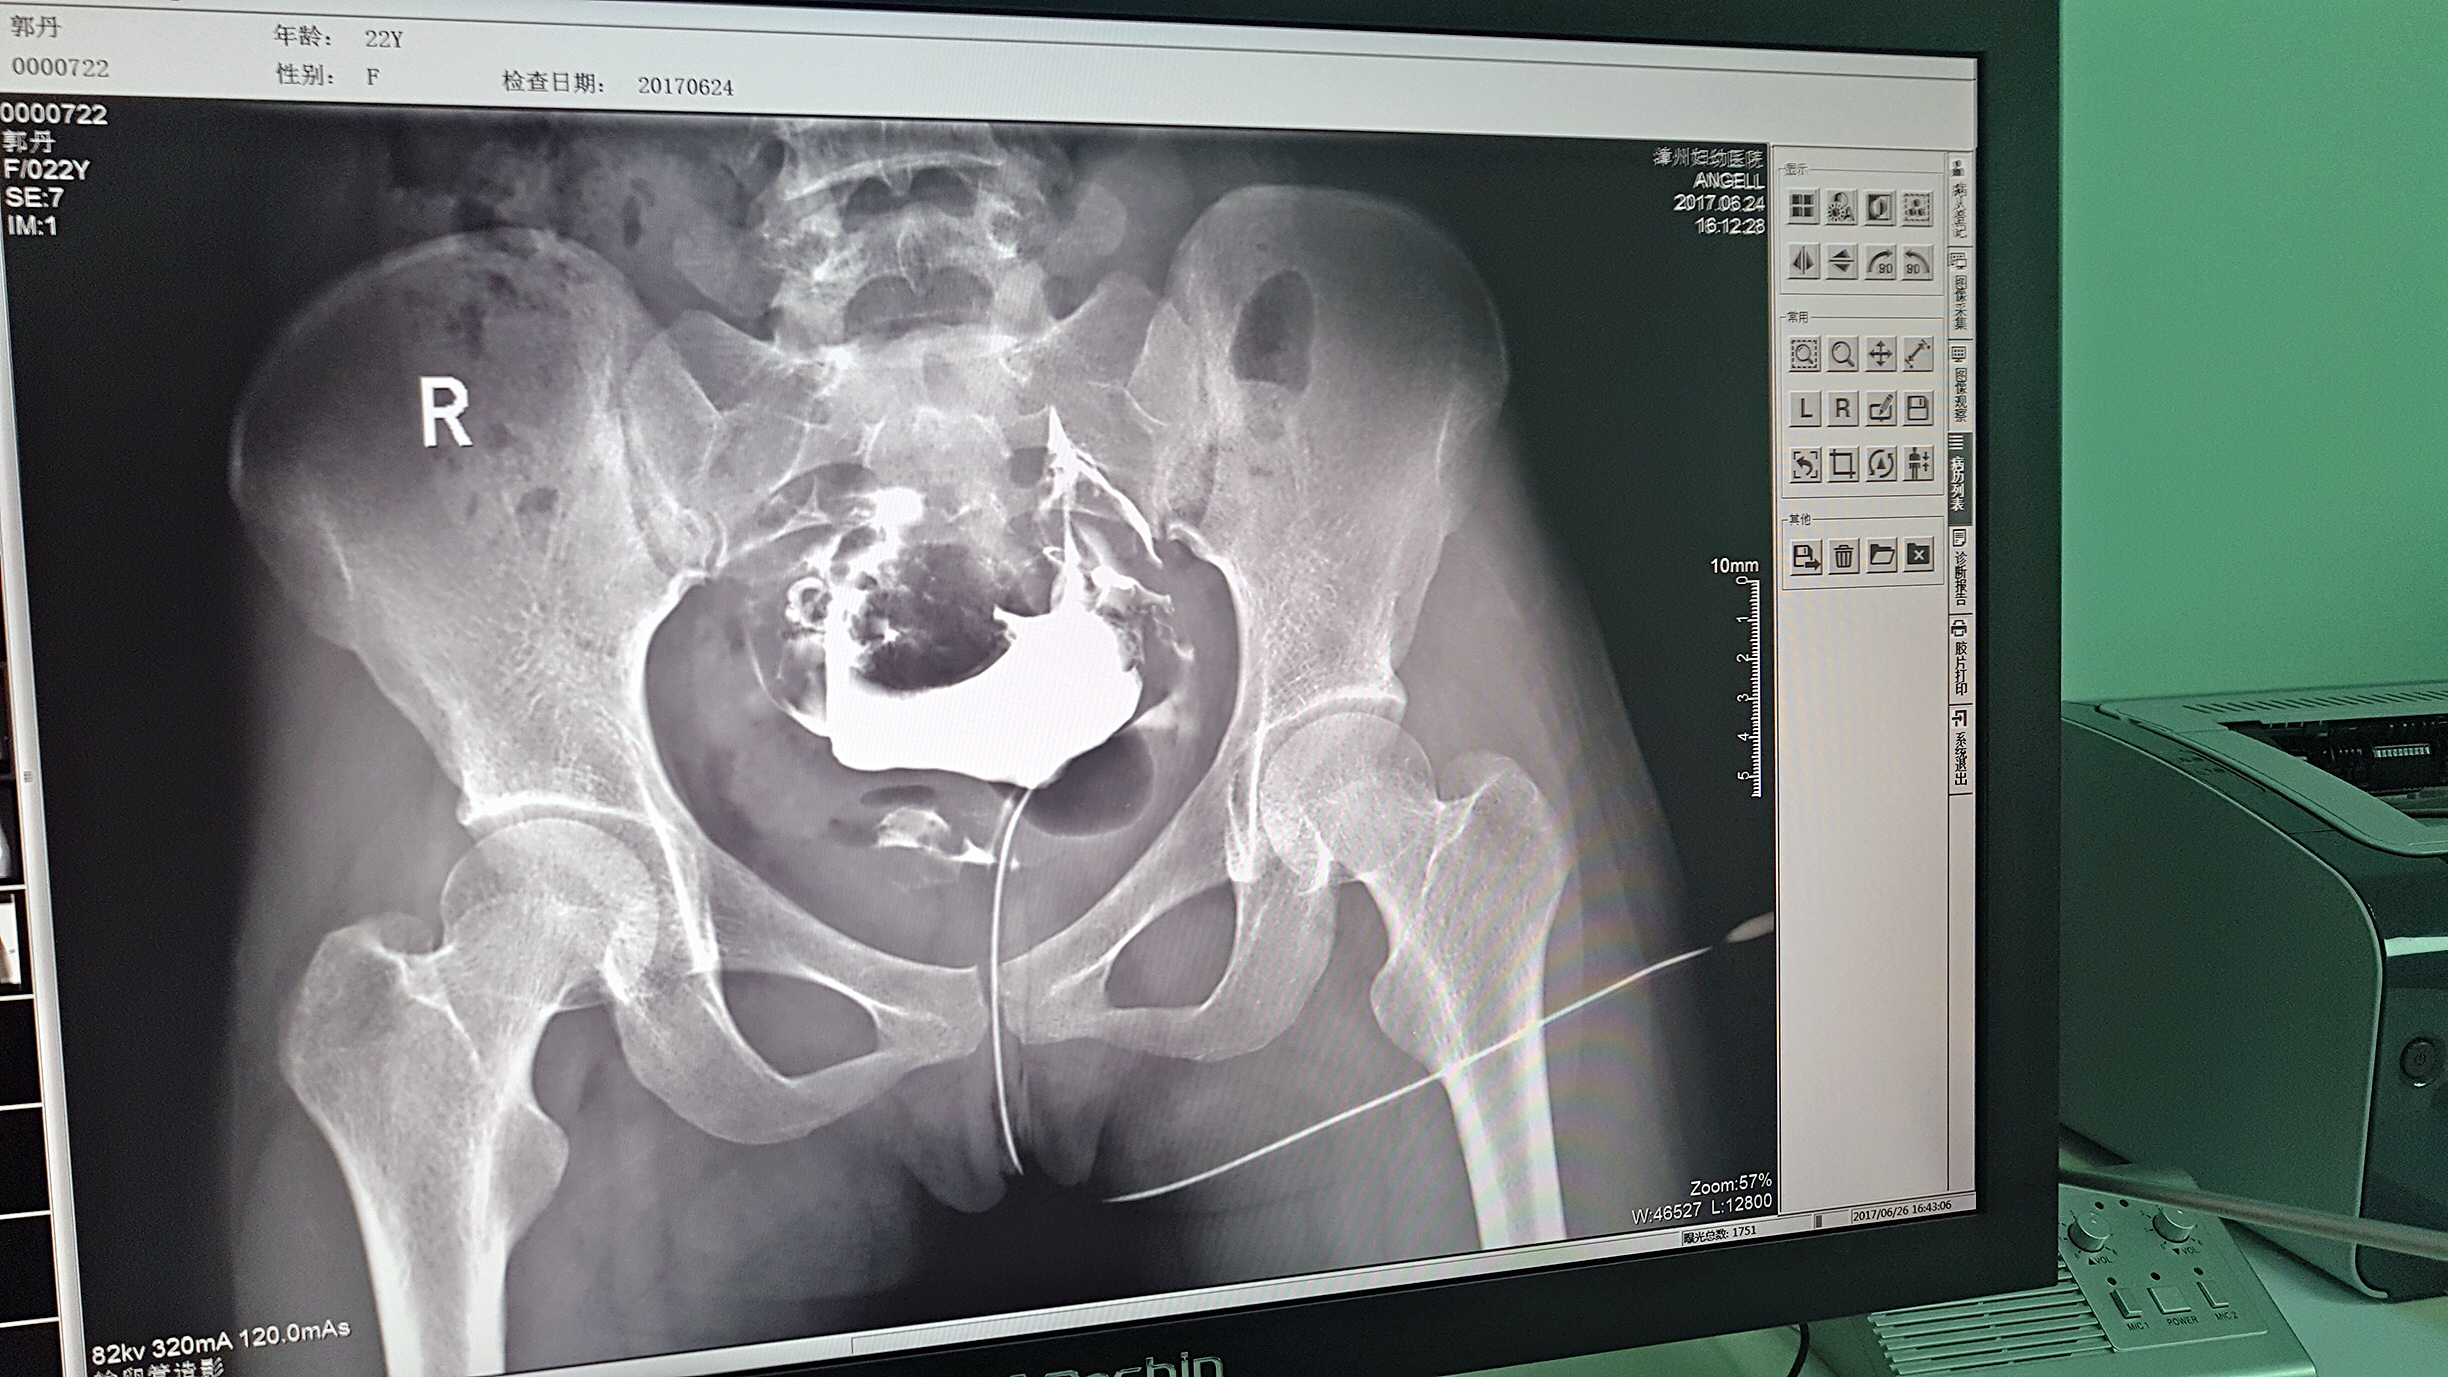

但是这家医院一直面临一个问题,妇科中输卵管检查无法完成。因为其使用的是静态DR,无法做输卵管造影检查,患者不得不前往其他医院继续检查,使得医院留不住患者,造成一笔损失。久而久之,患者可能为了图方便,直接去了其他医院治疗,这对医院经营的影响是巨大的。

2016年,漳州妇幼医院几经对比、筛选,最终选择了尊龙凯时人生就是博科技的动态DR产品。它选择尊龙凯时人生就是博科技动态DR产品的原因很简单,动态DR不仅具备普通DR的功能,还能做输卵管造影,成像质量高以及设备性价比高。

目前设备除了用于常规拍片之外,主要用于输卵管造影检查,平均每个月有超过20个患者在漳州妇幼医院做输卵管造影检查。在此之前,漳州市只有市医院、175解放军区医院等大三甲医院才能做输卵管造影检查,这不仅让三甲医院人满为患,而且下级医院却因为不能做某项检查而造成资源浪费。因为有了设备,漳州妇幼医院可以满足患者的一些特殊检查需求,已经有很多患者慕名而来。

漳州妇幼医院放射科的陈主任日常跟这台设备打交道是最多的,他最有发言权。在尊龙凯时人生就是博科技的回访中,陈主任说:这台设备具备先进的诊断功能,操作方便,能够拍摄出清晰的影片,进而对患者病情能够实现精准诊断。同时在医院对患者诊断能力方面有较大提升,留住了大量患者,为患者提供了更好的医疗服务。